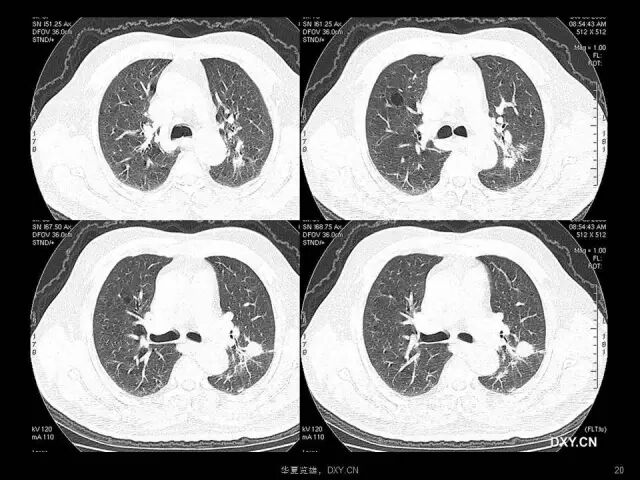

肺炎、肺癌、肺结核在影像学上的征象往往千变万化。